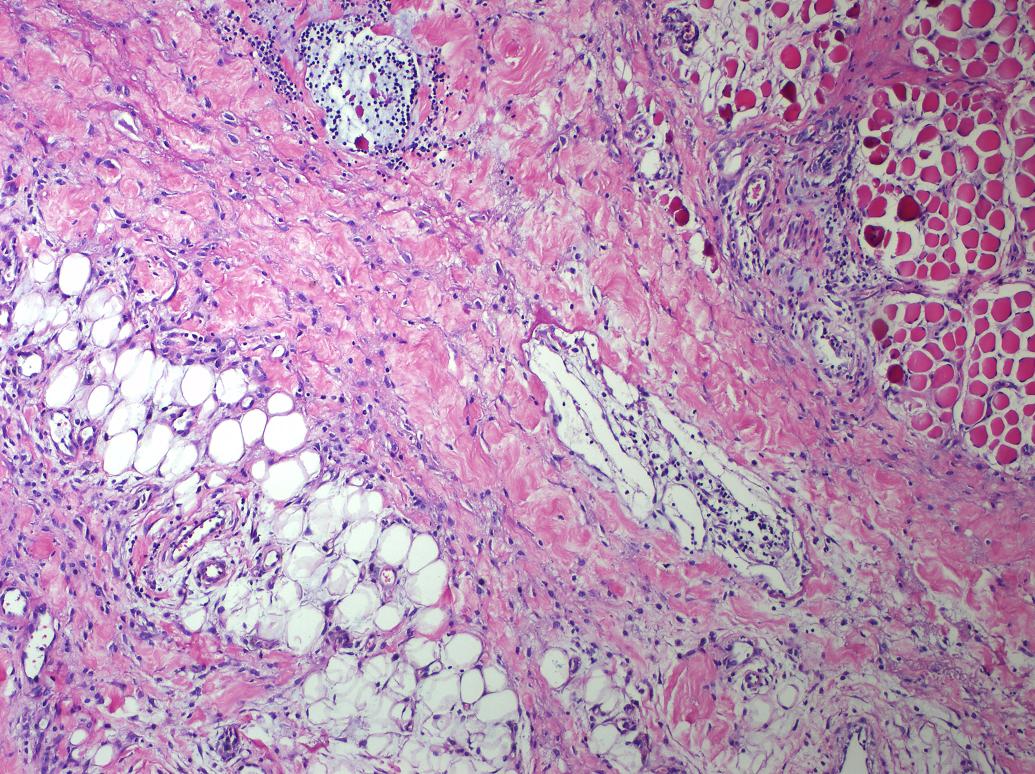

Cervical Lymphadenitis Due to Nodular Fasciitis in a Child

Nodular fasciitis is a benign, reactive proliferation of fibroblasts in the subcutaneous tissues. It usually affects the trunk and upper extremities, and rarely the head and neck region of young adults. It is rare among children and the histologic findings may incorrectly suggest malignant lesions. We describe a two-year-old girl that referred to our clinic with complaints of fever and swelling on the right side of neck and diagnosed as lymphadenitis clinically. Cervical lymphadenitis due to nodular fasciitis is a rarity. We emphasize that nodular fasciitis needs to be included in the differential diagnoses of neck lymphadenitis during childhood.